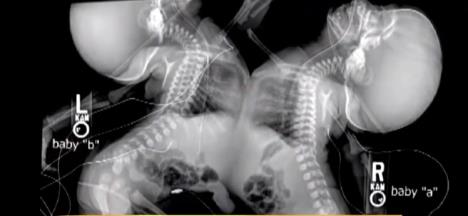

Međutim, u 20. nedelji se sve promenilo. Doktori su primetili da su bebe spojene i strahovali su da neće preživeti razdvajanje. Zbog toga su savetovali da prekine trudnoću.

Stopa preživljavanja sijamskih blizanaca je između 5 odsto i 25 odsto. U 75 odsto hirurških separacija preživi barem jedan blizanac.

Kad su devojčice imale 9 meseci, tim od 40 doktora je izveo operaciju koja je trajala punih 7 sati. Uspešno su razdvojili sestre.